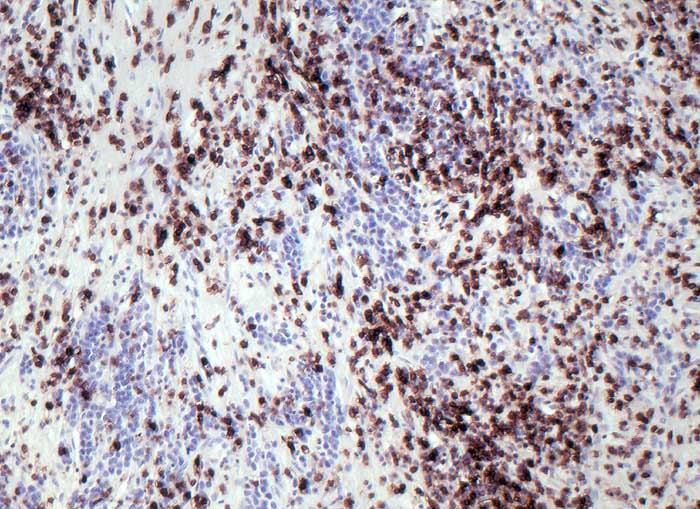

PathoPic ID 6469 - Lymphoepitheliom-artiges Magenkarzinom (medulläres Karzinom)

Lymphoepitheliom-artiges Magenkarzinom (medulläres Karzinom)

Die grösseren Tumorzellen reagieren nicht mit dem panleukozytären Marker CD45.

Magenstumpfkarzinom 20 Jahre nach Billroth II-Resektion wegen Ulcus duodeni.

Die Prognose bei fortgeschrittenen Tumoren ist wesentlich besser beim medullären Karzinom als bei konventionellen Adenokarzinomsubtypen des Magens.

Histologie

Immunhistochemie

CD45 (LCA)

320